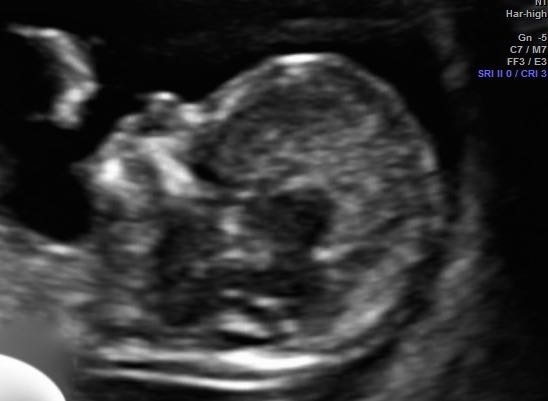

I've been on a bit of a rollercoaster. We had our NT ultrasound yesterday, at which everything looked just perfect. We were so heartened to see baby wiggling around in there like a hippie at a Grateful Dead concert in 1969.

Just love this little button-nose so much. All of a sudden, I can't shake the feeling it's a boy!